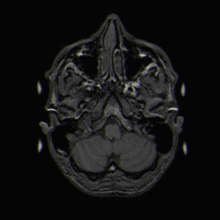

Wird nun das Magnetfeld ausgeschaltet, kehren die Kerne in ihre Ausgangsstellung zurück und geben dabei diese Energie in Form elektromagnetischer Wellen wieder ab. Diese Signale werden von hochempfindlichen Empfängern aus verschiedenen Richtungen registriert und per Computer in Schnittbilder (Tomogramme) umgesetzt.

Da die verschiedenen Gewebearten im Körper unterschiedliche Mengen an Wasser enthalten (z. B. Fettgewebe viel, Knochen wenig), geben sie mehr oder weniger Signale ab und stellen sich damit unterschiedlich, nämlich heller oder dunkler dar.